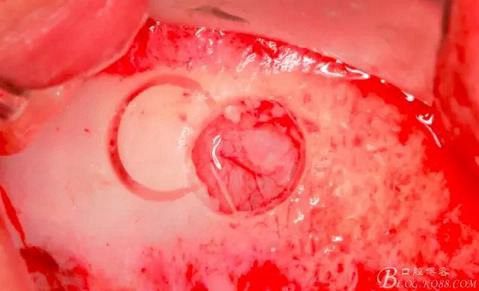

此時頰側(cè)竇膜與骨壁已經(jīng)分離,無需擔(dān)心開窗損傷竇膜。使用環(huán)切鉆以小洞口為中心開窗,轉(zhuǎn)速500轉(zhuǎn),為了保證安全,可以將種植機調(diào)成反轉(zhuǎn)模式,一樣有強大的切割效率。

因缺牙多,需要植骨的區(qū)域大,在遠中再環(huán)切一窗口。

使用窗口擴大鉆,這也是這套工具盒里一個亮點,其前端是圓形高度光滑的,鉆體是有側(cè)切功能的。工作時用光滑的圓頭頂開已經(jīng)剝離的竇膜,用鉆體部分將窗口周邊不規(guī)則的部分磨掉,同時可以擴大窗口。